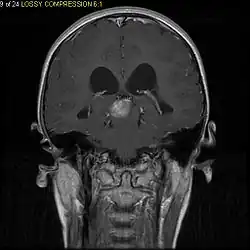

Usually – depending on the interview of the patient and after a clinical exam which includes a neurological exam and an ophthalmological exam – a CT scan and/or an MRI scan will be performed to confirm the presence of a tumor. They are usually easily distinguishable from normal brain structures using these imaging techniques. A special dye may be injected into a vein before these scans to provide contrast and make tumors easier to identify. Pilocytic astrocytomas are typically clearly visible on such scans, but it is often difficult to say based on imaging alone what type of tumor is present.